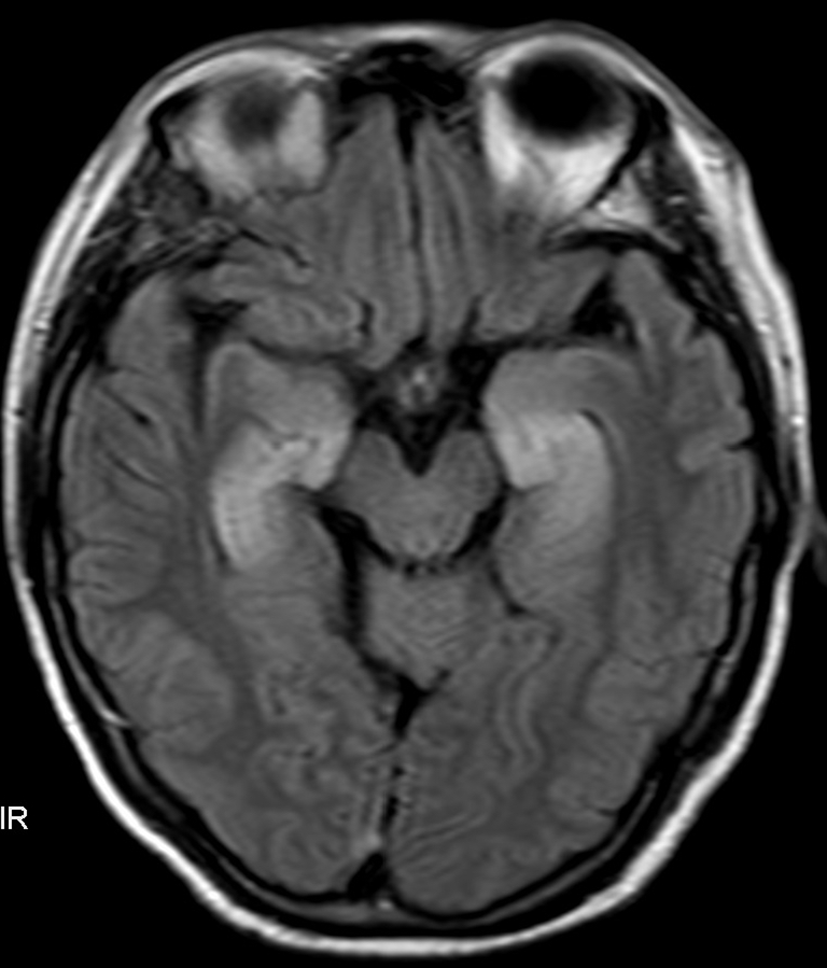

A 58-year-old female patient was admitted on September 7, 2021, because of shortness of breath, dizziness for 1 week, nausea, and vomiting for 4 days. The diagnosis was SCLC in the right lung with metastases to the mediastinum, right hilum, neck, axillary lymph nodes, and right pleura classified as T4bN3M1a (extensive stage). Starting on September 15, 2021, 120 mg etoposide on Days 1-3 plus 90 mg cisplatin on Day 1 via intravenous drip (every 3 weeks) was administered for six cycles. On January 19, 2022, an additional 1000 mg of D1 Q4W treatment with durvalumab (AstraZeneca UK Limited) was initiated. During this period, regular follow-up evaluations revealed partial remission (PR). After 19 cycles of durvalumab (July 1, 2023), the patient experienced seizures characterized by loss of consciousness, convulsions, foaming at the mouth, and clenched teeth lasting for approximately 1 min. Subsequently, progressive cognitive decline, increased sleep, decreased speech, and olfactory hallucinations occurred. After admission, the electrolyte test results showed Na+ at 114.2 mmol/L and Cl- at 82.2 mmol/L. Electroencephalography (EEG) revealed mild-to-moderate abnormalities characterized by an increase in slow waves. Fluid attenuation inversion recovery (FLAIR) magnetic resonance imaging of the head revealed high signal areas in the bilateral medial temporal lobe and hippocampus (Figure 1). A Mini-Mental State Examination score of 14/30 indicated moderate cognitive impairment. Lumbar puncture revealed a normal cerebrospinal fluid (CSF) cell count and protein and sugar levels. No malignant cells were found on the CSF cytological examination. Considering the possibility of encephalitis and paraneoplastic syndrome, CSF and serum samples were sent to the testing center for analysis. The results showed that oligoclonal bands were observed in serum and CSF. Positive anti-GABABR antibodies were detected in the serum and CSF samples. Paraneoplastic syndrome antibodies (anti-Hu, anti-Yo, anti-Ri, anti-CV2, anti-amphiphysin, anti-Ma1, anti-Ma2, anti-SOX1, anti-DNER, anti-Zic4, anti-GAD65, anti-PKC, anti-recoverin, and anti-titin) were negative in the serum and CSF, whereas other autoimmune encephalitis antibodies (anti-NMDA, anti-LGI1, anti-CASPR2, anti-AMPAR1, and anti-AMPAR2) were negative in the serum and were not detected because of insufficient CSF samples. On the basis of these results, the patient was diagnosed with durvalumab-induced anti-GABABR antibody-associated encephalitis. Therefore, durvalumab was discontinued and the patient began receiving 22.5 g of immunoglobulin (0.4 g/kg) daily and 1000 mg of methylprednisolone sodium succinate daily for 5 days. Additionally, 0.25 g of levetiracetam was administered twice daily to prevent seizures and correct electrolyte imbalance. After medication, the patient did not experience seizures, but cognitive impairment gradually increased. The patient finally died on November 2023 owing to pancreatic metastasis from SCLC.

Figure 1

Fluid attenuation inversion recovery (FLAIR) magnetic resonance imaging of the head revealed high signal areas in the bilateral medial temporal lobe and hippocampus.